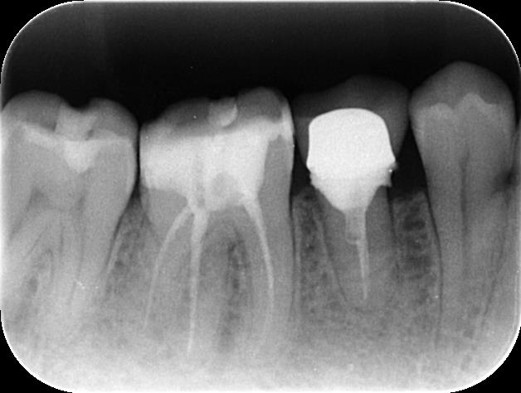

エクストルージョン症例:40代男性:虫歯を治したい。

治療前 ![]() |

カウンセリング・診断結果 |

虫歯が歯茎の下まで深く進んでおり、通常であれば抜歯を避けられない状態ですが、矯正の力で歯を数ミリ引っ張り上げる「エクストルージョン」という処置を行えば、ご自身の歯を残せる可能性があります。 |